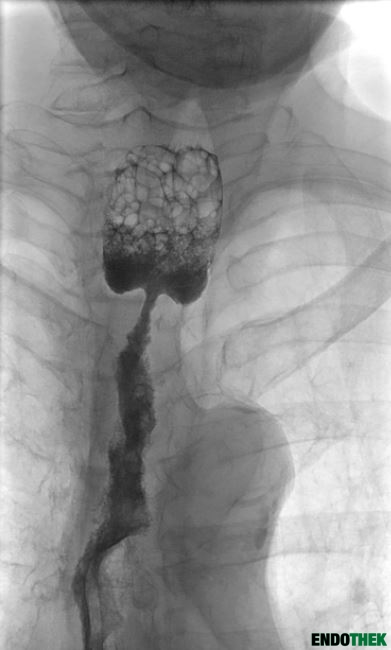

Peptische Ösophagusstenose mit Stentlegung